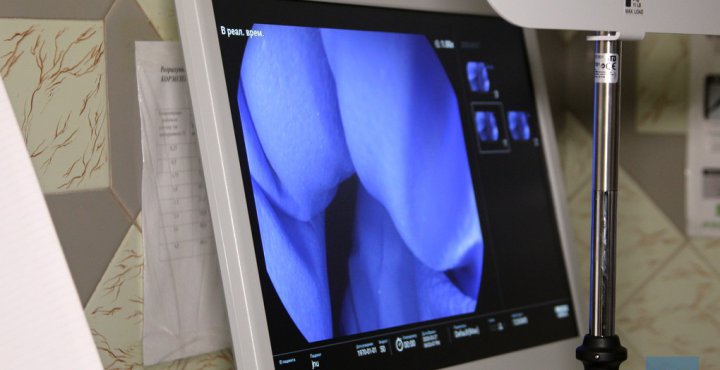

27-го березня у Володимир-Волинській лікарні встановлювали нове обладання. Комунальному підприємству «Володимир-Волинське територіальне медичне об’єднання» за кошти міського бюджету придбано відеогастроскоп і відеоколоноскоп фірми Pentax Medical (Японія) вартістю 2 мільйони 296 тисяч гривень. Обладання дасть можливість підписати ще один договір з НСЗУ і надавати якісні послуги пацієнтам.

Закуплена техніка дає можливість проводити ендоскопічні обстеження на високому рівні та полегшує діагностику різноманітних захворювань шлунково-кишкового тракту.

Обидва апарати потрібні для діагностики верхніх та нижніх відділів шлунково-кишкового тракту: відеогастроскоп та відеоколоноскоп допоможуть у верифікації діагнозів в гастроентерології, терапії та хірургії. Це високоякісне обладнання розширює спектр роботи лікаря-ендоскопіста від діагностичних до лікувальних процедур.

Медтехніка дасть змогу якісно і вчасно виявляти захворювання гастроентерологічного профілю та онкопатологію на ранніх стадіях серед населення.